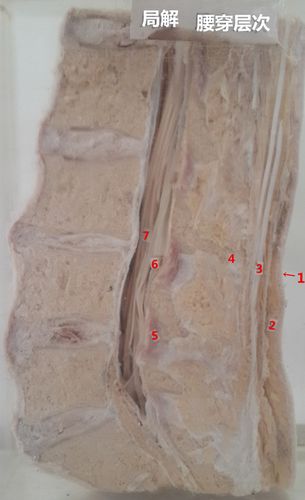

腰穿解剖层次图解

腰穿解剖层次图解,腰穿层次图

腰穿层次图

腰穿经过的层次结构图

腰穿解剖层次

腰穿解剖图解

腰穿层次示意图

腰椎穿刺层次图